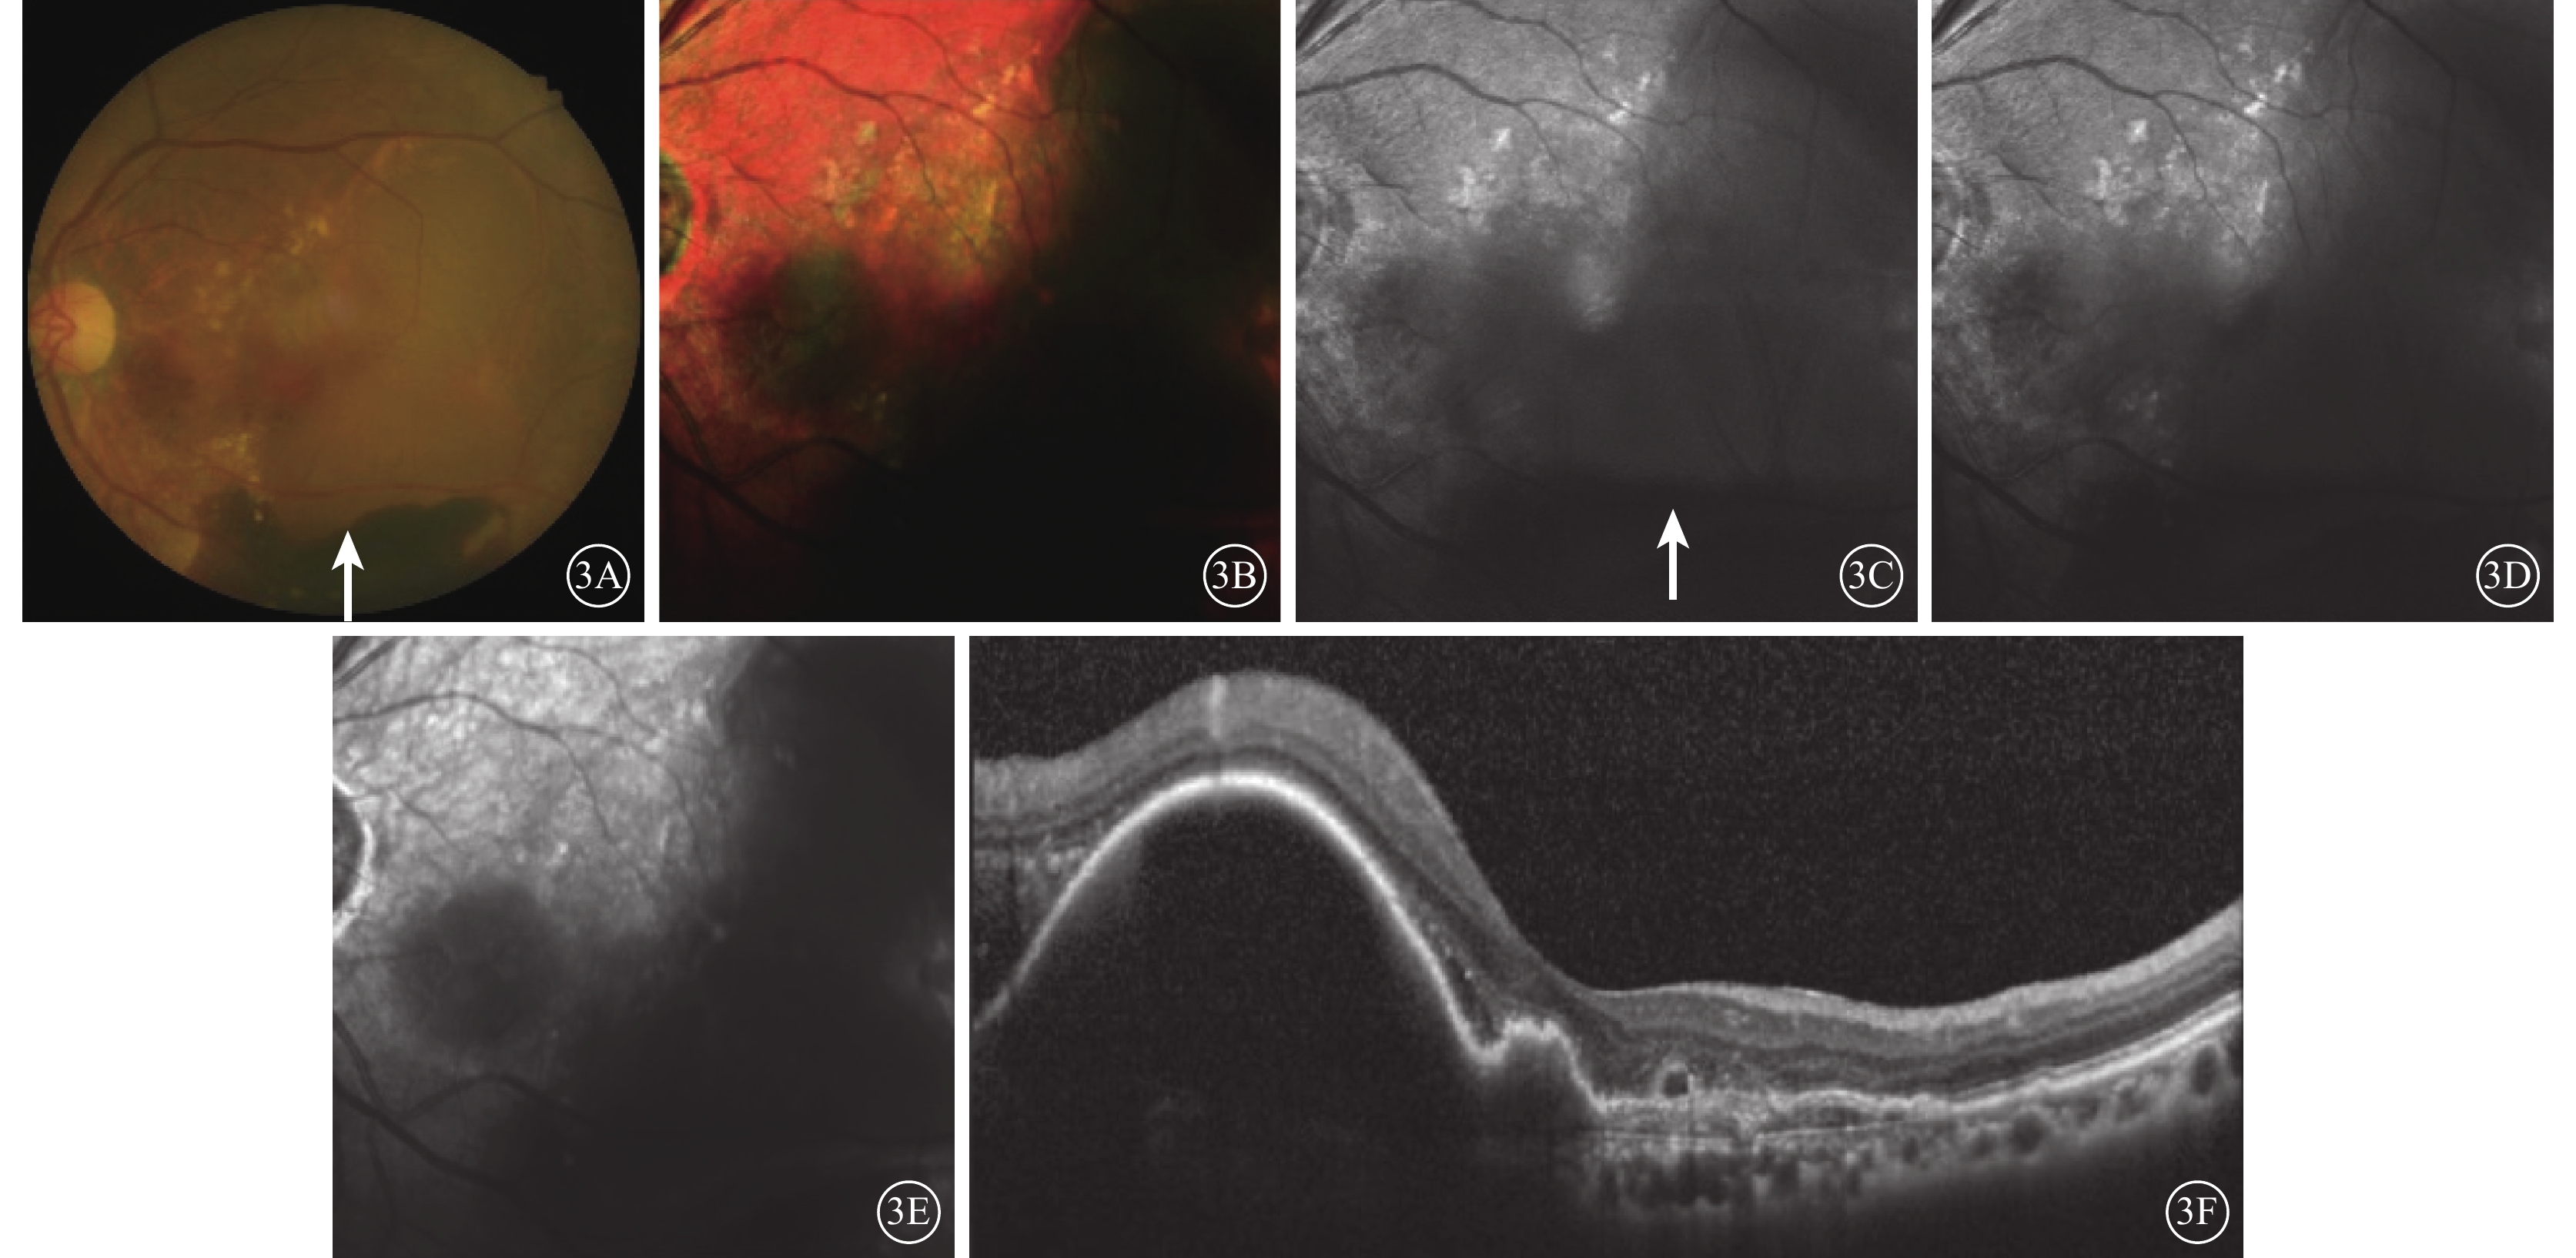

經多模式成像綜合判斷,32只眼中,漿液性PED(圖1)20只眼,出血性PED 3只眼,漿液性合并出血性PED 9只眼。

漿液性PED患眼FFA聯合ICGA像。1A示FFA像,可見黃斑下方局部有滲漏;1B示ICGA像,可見黃斑下方脈絡膜異常血管網

圖1

漿液性PED患眼FFA聯合ICGA像。1A示FFA像,可見黃斑下方局部有滲漏;1B示ICGA像,可見黃斑下方脈絡膜異常血管網

經多模式成像綜合判斷,32只眼中,漿液性PED(圖1)20只眼,出血性PED 3只眼,漿液性合并出血性PED 9只眼。

漿液性PED患眼FFA聯合ICGA像。1A示FFA像,可見黃斑下方局部有滲漏;1B示ICGA像,可見黃斑下方脈絡膜異常血管網

圖1

漿液性PED患眼FFA聯合ICGA像。1A示FFA像,可見黃斑下方局部有滲漏;1B示ICGA像,可見黃斑下方脈絡膜異常血管網